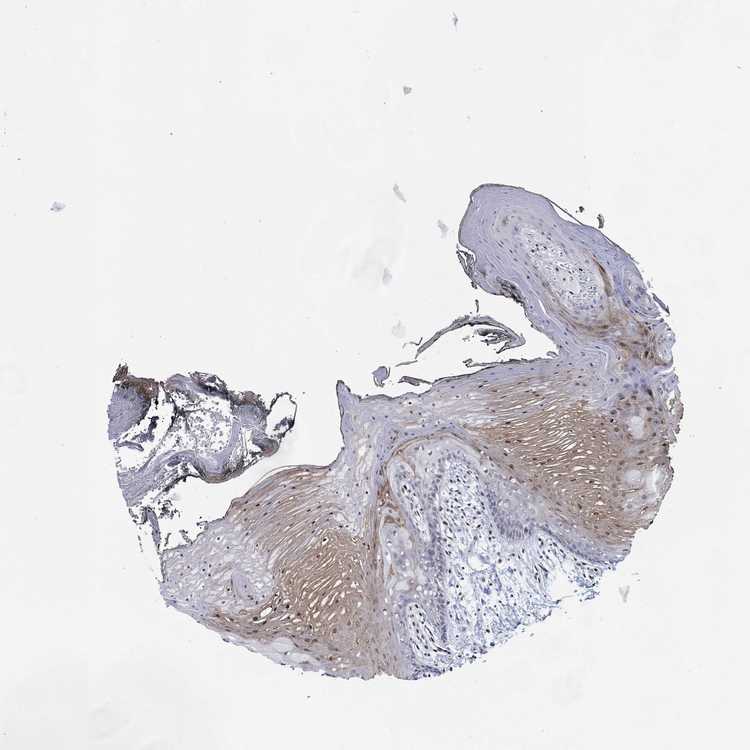

TISSUE PRIMARY DATA ORAL MUCOSA Show tissue menu

ORAL MUCOSA - Antibody stainingi

Antibody staining in the annotated cell types in the current human tissue is reported as not detected, low, medium, or high, based on conventional immunohistochemistry profiling in selected tissues. This score is based on the combination of the staining intensity and fraction of stained cells.

Each image is clickable and will lead to virtual microscopy that enables deeper exploration of all samples and also displays staining intensity scores, fraction scores and subcellular localization as well as patient and tissue information for each sample.

Antibody HPA027524Antibody CAB058686Antibody CAB079943

Squamous epithelial cells LowNot detectedNot detected